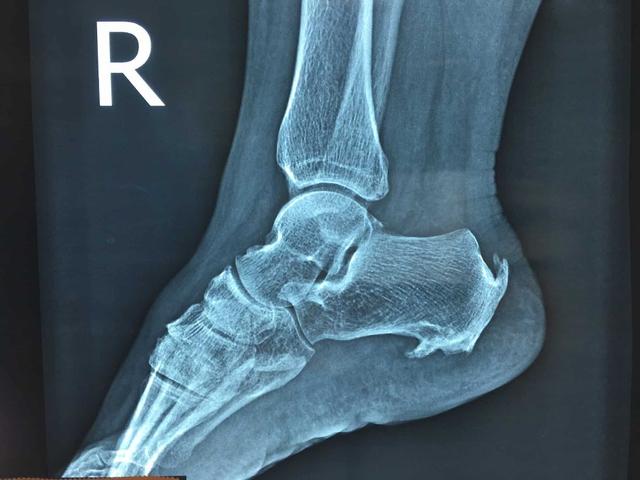

另外一个问题我们要谈一下,那就是关于我们因为足跟痛到医院进行X线检查,发现存在跟骨骨刺的问题。

我们很多人都认为是这个骨刺让我们导致的症状,其实不然!这个位置是跟腱或者是跖腱膜与骨骼连接的地方,正是由于长期的劳损导致这个位置出现了损伤、纤维结构撕裂甚至出血等情况,这些问题没有被好好的吸收,最终变成了钙化,逐渐随着时间的延长,变成了跟骨骨刺。

所以跟骨骨刺并不是导致我们疼痛的原因,大家可以想一下这个骨刺不是一天形成的,很有可能已经有了几年甚至十几年的时间了,但您的疼痛才几个月或者是几天而已。

纠结于治疗骨刺,甚至想要切除跟骨骨折,并不能帮助我们缓解症状,这一点请大家要切记,而且有大量的研究也证明,跟骨骨刺导致患者出现足跟痛的比率仅仅占6%左右,可以说非常的低。